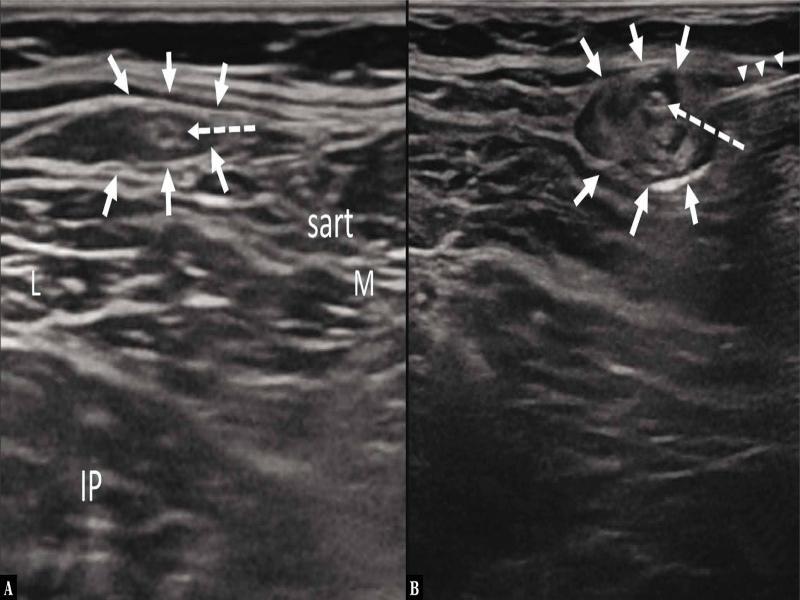

Fig. 1.